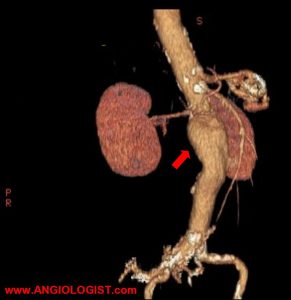

In the past, the only options for abdominal aortic aneurysm treatment were surveillance or surgery. Today endovascular repair of aortic aneurysms is usually the treatment of choice. Of course, choosing between surveillance, endovascular and surgical repair can be hard. It requires an understanding of the natural history of AAA as well as the short and…